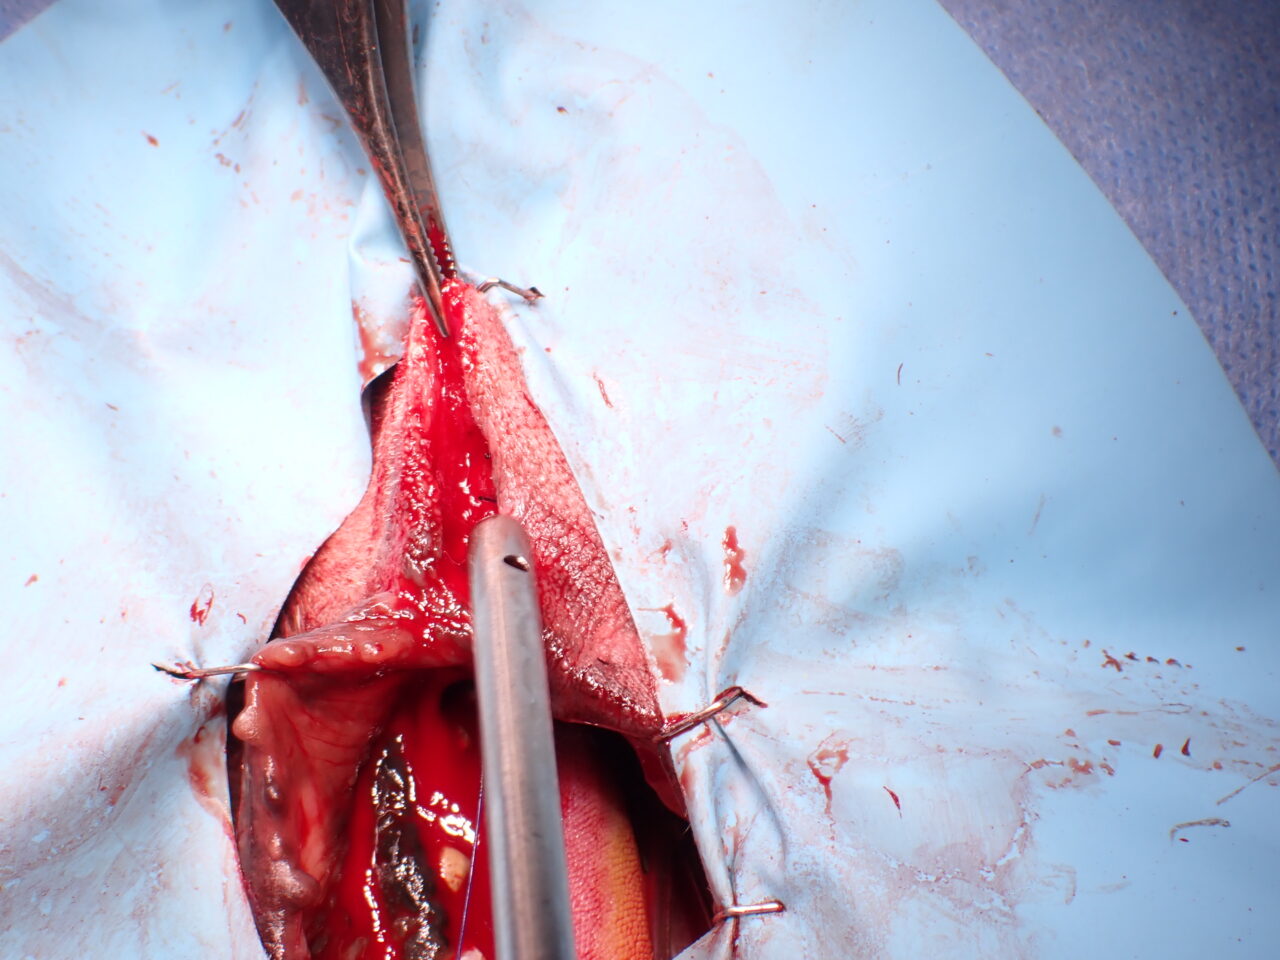

口唇部メラノーマ Wedge Resection Technique

- 腫瘍の切除:

口唇部のWedge Resection Technique

マージン確保 - 形成外科的再建:

- Wedge Resection Techniqueを使用して口唇の欠損を再建。